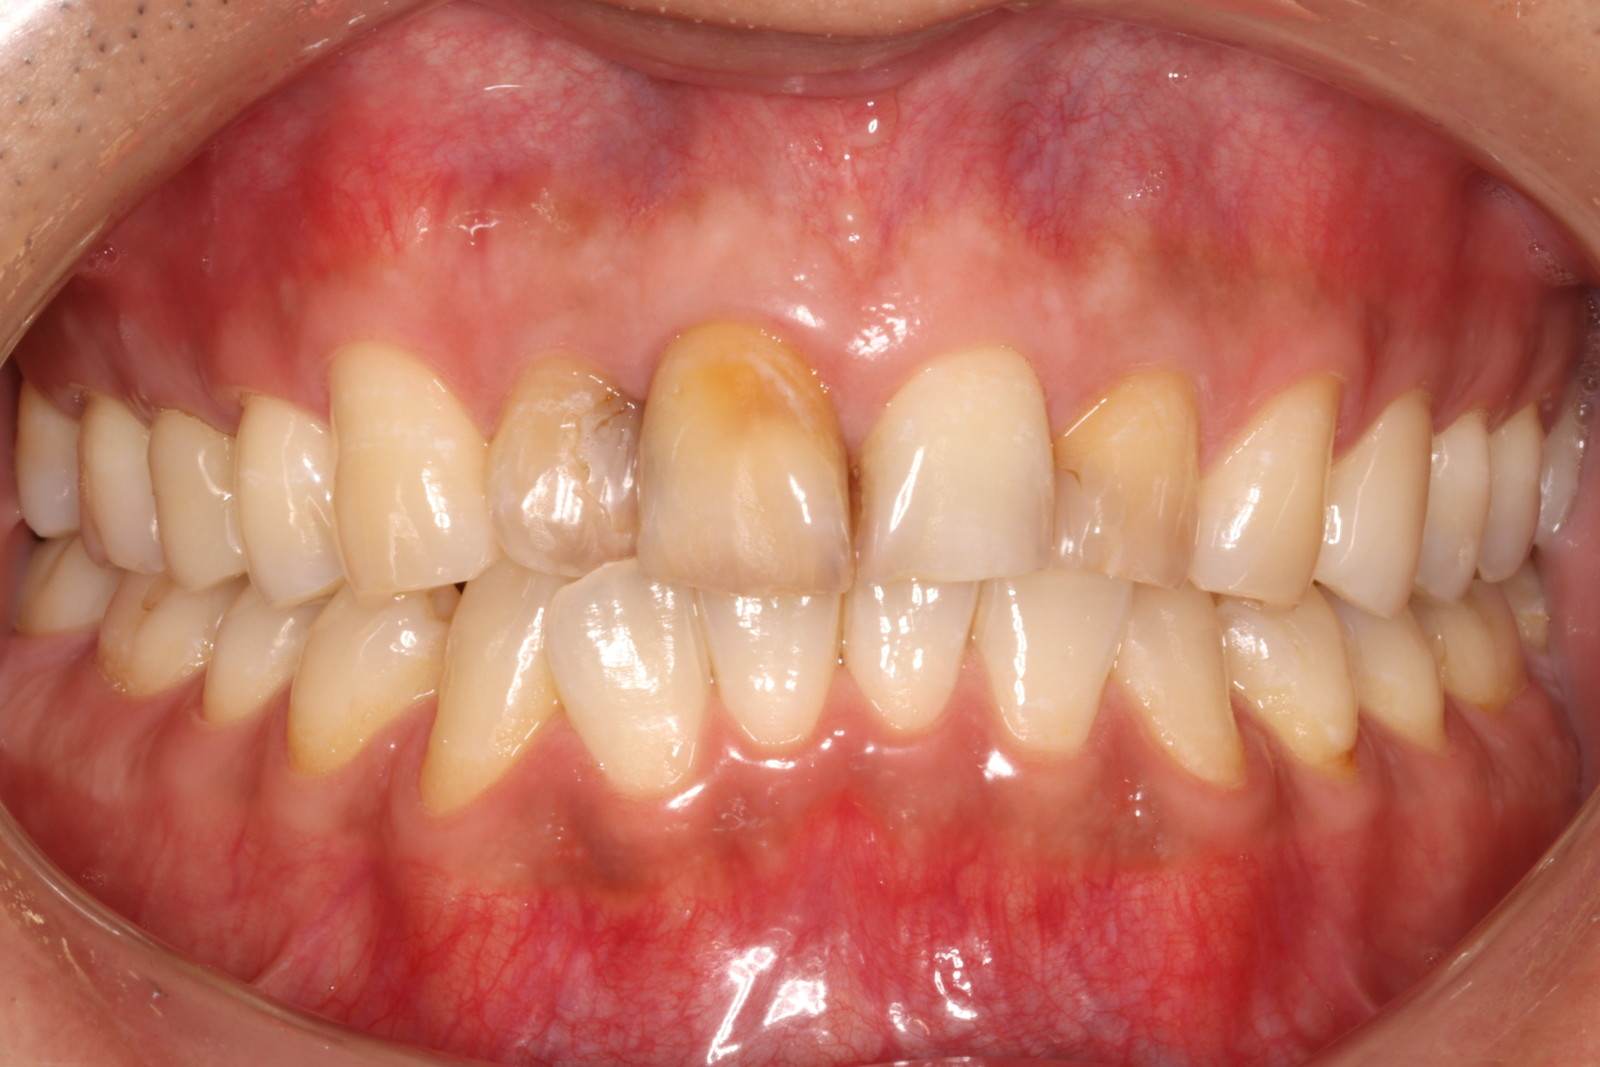

一般的に、歯並びを整える方法としては「歯列矯正」があり、歯の形や色を整える方法として

は「セラミック治療」があります。

当院では、これらを組み合わせた「セラミック矯正」を提供しています。具体的には、セラミックの被せ物を使って歯の形や色を整えながら、同時に歯並びも改善していきます。

しかし、その一方で「健康な歯を削る」必要があります。セラミックの被せ物を装着するためには、どうしても天然歯を削らなければなりません。